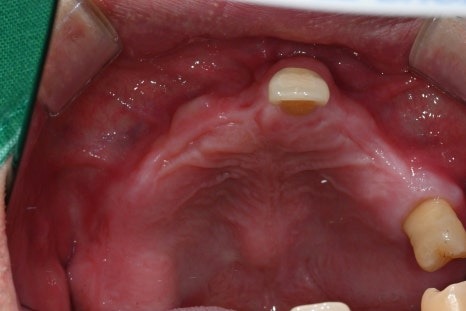

· 상악은 잇몸뼈가 매우 얇고 치아가 거의 남아 있지 않은 상태

· 상악 양측 상악동 거상술 + 임플란트 10개 식립

임시치아부터 최종 보철까지의 과정

수술 직후에는

임시틀니 대신 고정형 임시치아를 적용하여

일상생활과 식사 불편을 최대한 줄였습니다.

· 수술 다음 날 임시치아 장착